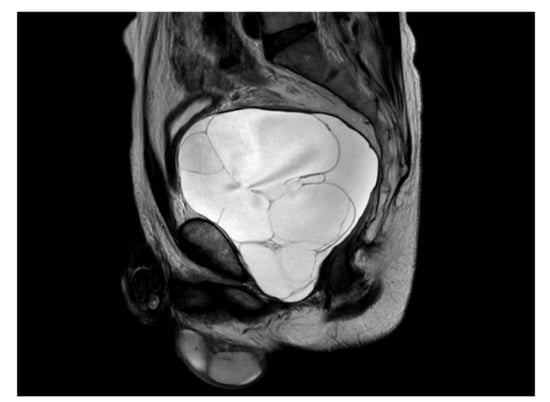

A previously healthy 54-year-old man presented with acute urinary retention. The patient also presented with weak stream, tenesmus, hesitancy, and intermittency. On digital rectal examination, the enlarged prostate was palpated softly, and no nodules were detected. His PSA level was 0.469 ng/mL. Prostate MRI showed a large cystic mass approximately 13 cm in size, multiple septa and lobulation in the prostate, and no visible solid lesions (Figure 1). The urinary bladder and rectum were displaced as a result of the enlarged cystic prostatic mass.

Figure 1.

Prostate MRI showed a large cystic mass approximately 13 cm in size, multiple septa and lobulating contours in the prostate, and no visible solid lesions.